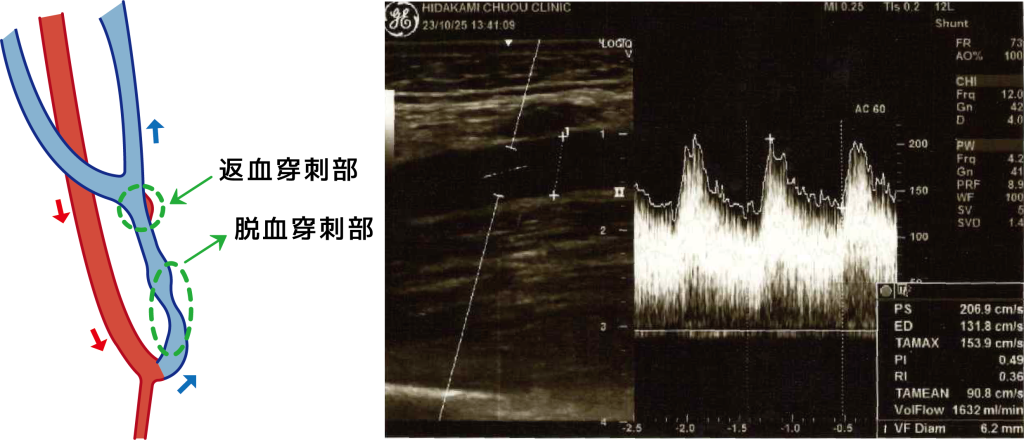

血液透析とは、内シャントを作成した後、太くなった静脈に2本の針を刺して、体内の血液を体外循環しながら、ダイアライザーと呼ばれる血液透析器で血液をきれいにし、水分除去を行う治療です。このダイアライザーは、人工の腎臓のような働きをしますので、人工腎臓と言われています。つまり、血液中の尿毒症物質を拡散という方法で除去し、除水も行います。

人工透析とは、体から一分間に150ml~200mlの血液を抜き出し、体に溜まった水分や老廃物を除去し戻す治療です。そのため血液を抜き出し、戻す出入り口が必要となります。その出入り口のことを「バスキュラーアクセス」と言います。以下のような方法があり、どの方法も良いところ悪いところがあります。

1.内シャント(自己血管シャント)

もっとも一般的な方法です。

自分の動脈と静脈を手術でつなぎ合わせることで、血流の多い静脈(シャント血管)を作ります。

この血管を透析時に針で穿刺します(穿刺は、事前に麻酔薬のついたシールを皮膚に貼って痛みが軽減するように工夫しています)。